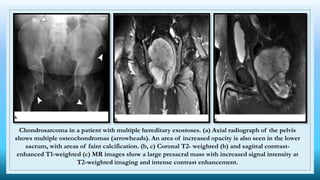

Chondrosarcoma in a patient with multiple hereditary exostoses. (a) Axial radiograph of the pelvis

shows multiple osteochondromas (arrowheads). An area of increased opacity is also seen in the lower

sacrum, with areas of faint calcification. (b, c) Coronal T2- weighted (b) and sagittal contrast-

enhanced T1-weighted (c) MR images show a large presacral mass with increased signal intensity at

T2-weighted imaging and intense contrast enhancement.